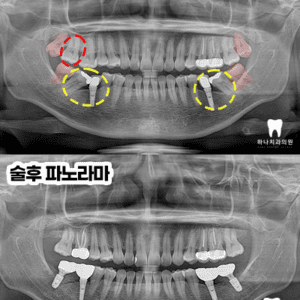

울산삼산동치과 염증으로 인한 타 치과 임플란트 제거 후 재수복

울산삼산동치과 염증으로 인한 타 치과 임플란트 제거 후 재수복   안녕하세요! 하나치과입니다~:) ​ 임플란트는 잃어버린 치아의 저작 기능과 심미성을 회복하는 대표적 치료법으로 자리 잡았지만 모든 케이스가 같은 조건을 가지는 것은 아닌데요. ​ 발치 후 오랜 기간 방치되거나 잇몸뼈가 염증으로 소실된 경우에는 뼈이식, 상악동 거상술 등 추가적이고 복합적인 수술이 필요해 난이도가 더보기…